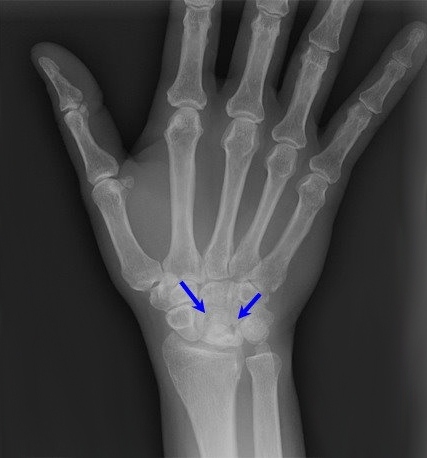

Рентгеннограмма при болезни Кинбека